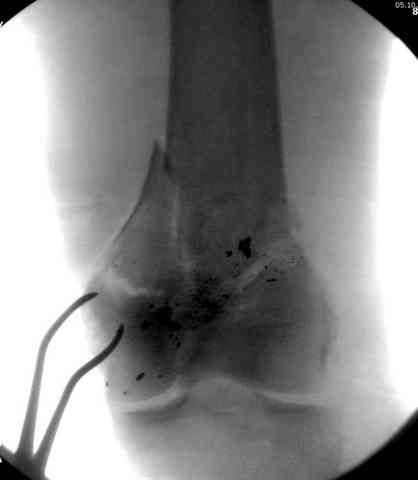

Условием для обязательного удаления пули считаем ее внутрисуставное расположение из-за возможного сатурнизма, или когда во время операции она без труда удаляется, а также поверхностно расположена.

2 внутрисуставной перелом дистального бедра с удалением пули